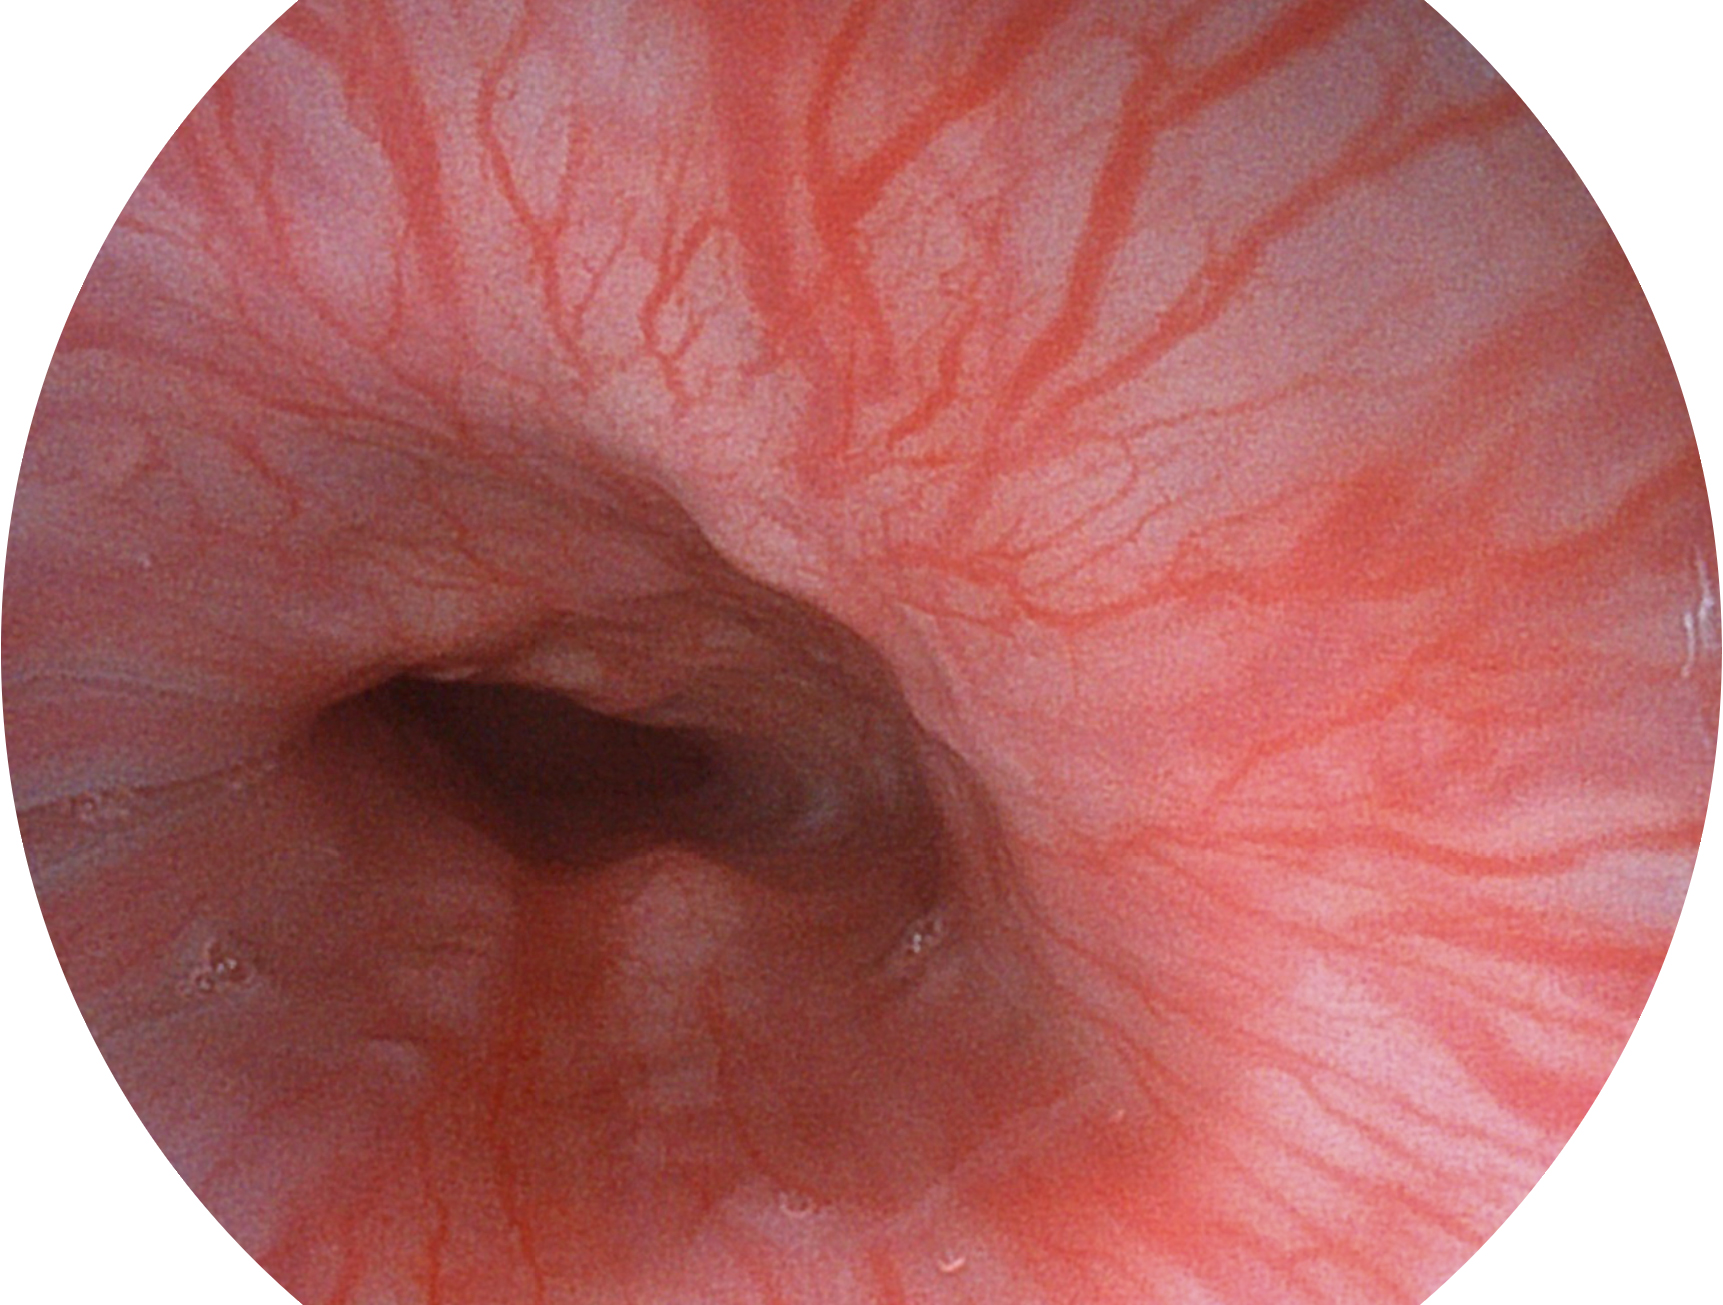

助力消化道早期疾病诊断

百老汇电子游戏官网新开发的内镜染色技术,主要是基于多波长LED 光源的开发,VLS-55Q 四波长LED 光源是由四个不同颜色的LED光按照相应照明模式所规定的特定发光比例进行合束后形成,合束后形成的照明光的光谱由红光、绿光、蓝光及蓝紫光这四个不同的波段范围构成。具有更高光谱自由度,通过光谱比例的控制,实现了聚谱成像技术,英文全称为“Spectral Focused Imaging, SFI”,缩写为“SFI”和光电复合染色成像技术,英文全称为“Versatile Intelligent Staining Technology, VIST”,缩写为“VIST”。